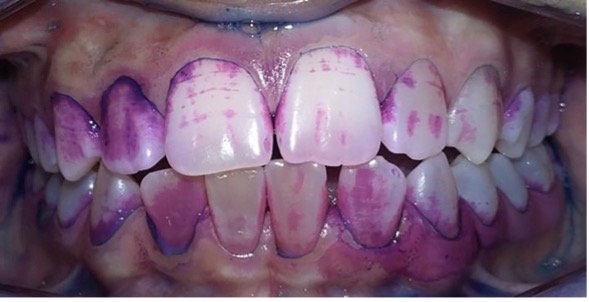

Control de placa bacteriana con revelador doble tono.

Aplicación de barniz de fluoruro de sodio.

Figura 9: Controles integrales periódicos

En el último control realizado en el año 2018 (Figura 11) el paciente mantuvo el estado de salud logrado. El análisis cariogénico fue moderado (por su historia pasada de caries y su condición biológica específica) y el gingivoperiodontal bajo. El paciente continúa en atención en la COIN. Fue derivado en varias oportunidades al servicio de Ortodoncia de la Facultad de Odontología de la Universidad de Buenos Aires, pero hasta el momento no encaró ningún tratamiento propuesto.